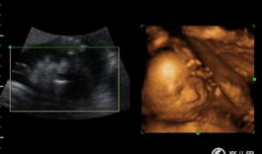

四维视频,四维视频揭示的视觉奇观与未来科技展望

哇,你有没有想过,未来看电影会是什么样子?想象你戴上眼镜,眼前不再是平面的画面,而是一个立体的世界,仿佛你真的置身其中。这就是四...